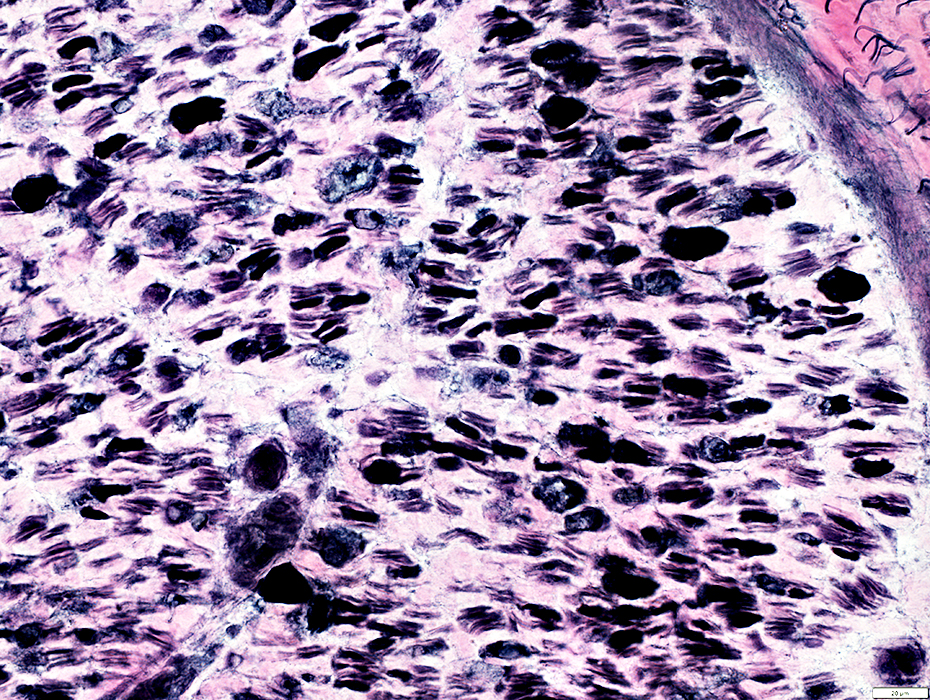

H&E stain

Myelinated Axons

Reduced number

Damaged myelin (Loss of staining)